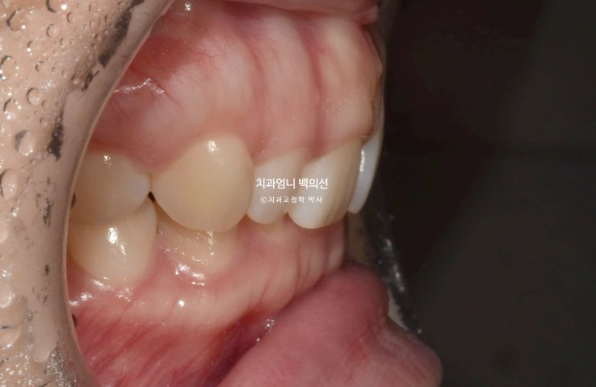

앞니가 뒤로 쓰러진 옥니이고

앞니가 옥니로 뒤로 쓰러져 있으면 앞니 뿌리 잇몸이 상대적으로 튀어나와 보이게 되며 잇몸돌출처럼 보이게 됩니다.

입술 돌출은 없어서 사랑니를 빼고 미니스크류를 심어서 사랑니 공간으로 어금니를 뒤로 밀어내는 비발치 치료계획을 세웠습니다.

치료 목표는 앞니 각도를 개선하며 함입시켜 거미스마일과 과개교합을 해결하는 것, 초진에서 보이는 잇몸 비대칭은 교정 후 잇몸성형이 필수인 점도 설명 드렸고 클리피씨 교정으로 치료 시작했습니다.